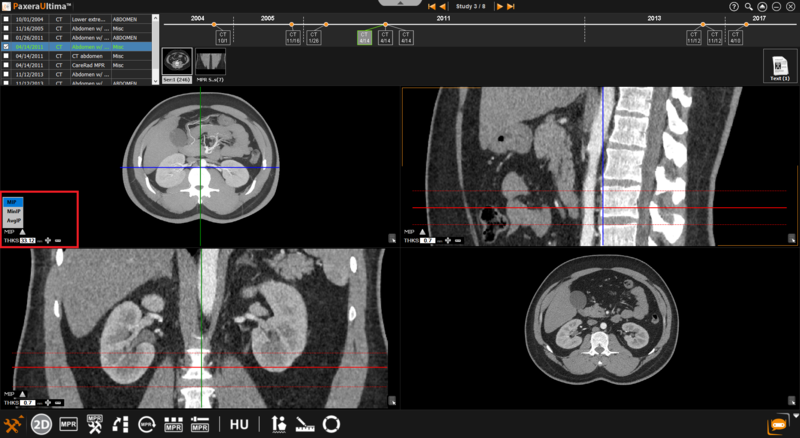

The MIP function is situated in the bottom left corner of each image window, as shown below:

The user can choose the intensity projection mode from maximum, minimum, or average: